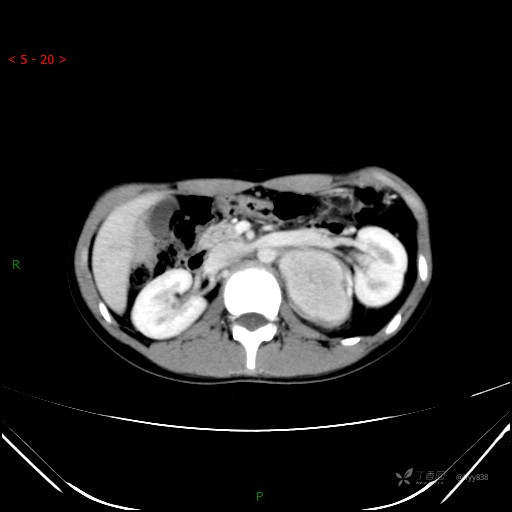

增强静脉期